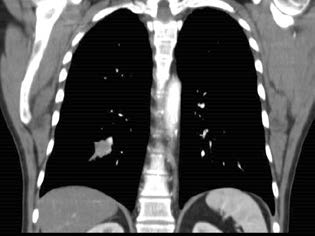

El informe del TAC de cuello y tórax: múltiples adenopatías en cadena yugulo-carotideas bilaterales, las mayores de 24 mm izquierdas y de 21 mm derechas de eje mayor. No hay signos de recidiva local. En el pulmón se aprecia una tumoración como nódulo espiculado en el lóbulo inferior derecho que dado el antecedente de cáncer de amígdala izquierda se considera metastásico. El paciente es derivado a la comisión oncológica, para valoración por cirugía torácica.

FIGURA 2: Corte coronal tomográfico, donde se observa la lesión en pulmón derecho.